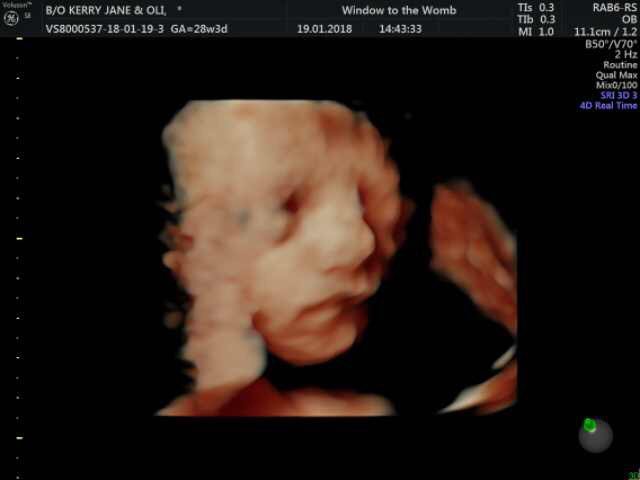

Our Bexleyheath clinic had the pleasure of welcoming actor Oli Regan and his partner into their clinic for a 4D HDlive scan.

Opting for a 4D + Well-being (Born to Be a Star) package with HDlive, Oli and partner began with a well-being check of baby in 2D, where our sonographers took a peek at little one and check all is well. All our scans include a diagnostic report to take away. Then they were introduced to little one in 4D! Our 4D + Well-being Package (Born to Be a Star) includes a scan movie recording, photo prints and lots more! Bexleyheath is one of a selection of our clinics who do HDlive scanning – the latest technology which gives you an even clearer image of baby.

Oli & partner were introduced to baby in HDlive!